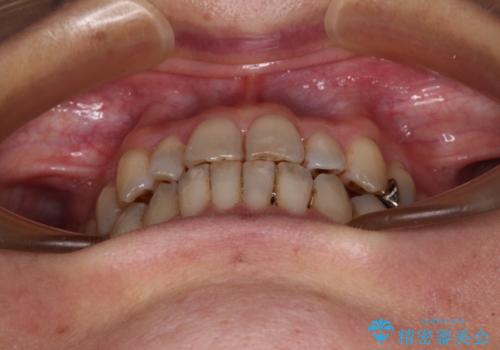

急速拡大装置 前歯の反対咬合をインビザラインで改善

上顎骨の幅が下顎骨よりも小さいので、拡大装置により骨幅を広げて上下関係を改善すると同時にワイヤー矯正で反対咬合の改善を図り、その後インビザラインにて歯並びを整えることとしました。

上顎前歯の矮小歯は矯正治療の途中でオールセラミッククラウンを装着し、左右のバランスを整えることとしました。

急速拡大装置の使用により奥歯の咬み合わせが劇的に変わり、その変化を利用して反対咬合を改善することができました。

治療期間中は奥歯が咬み合わず、食事が取りにくいなどの不都合がありましたが、最終的にはきれいに整えることができました。